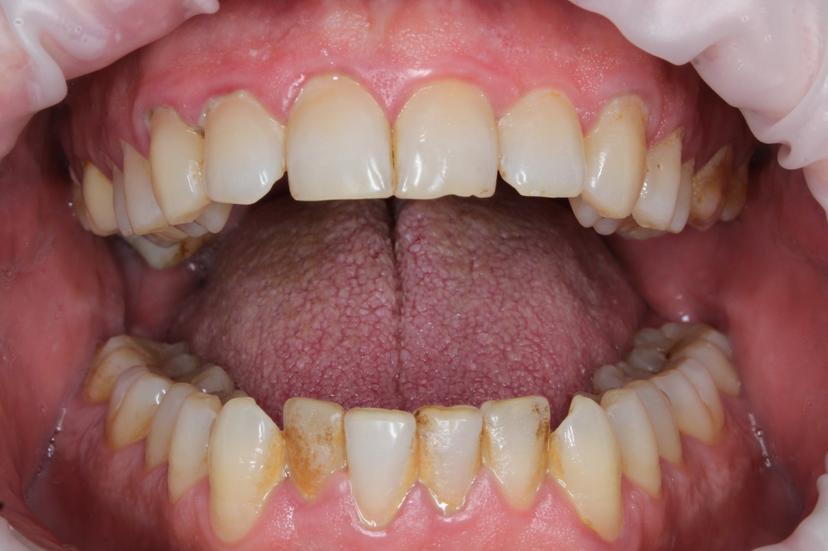

Пациент пришел с жалобами на неприятный запах изо рта и на темный налёт, который не убирается зубной щеткой.

Для снятия зубных отложений мы провели комплексную профилактическую гигиену с применениям ультразвука, AIR FLOW, щетки с пастой.

ДО: Заметны налет, пигментация и твердые зубные отложения, что придает неухоженный вид зубам.

После: Поверхность зубов очищена, восстановлен их естественный цвет, отсутствуют твердые зубные отложения и налет. Зубы выглядят здоровыми и ухоженными, а десны - свежими и более розовыми.